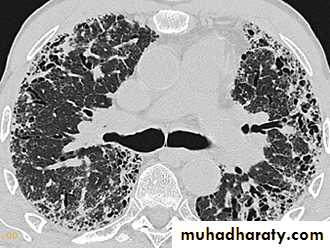

HRCT: reticulonodular shadowing in early stage and honeycomb cysts and traction bronchiectasis in advance stage.

HRCT may be diagnostic, demonstrating a patchy, predominantly peripheral, subpleural and basal reticular pattern with subpleural cysts (honeycombing).